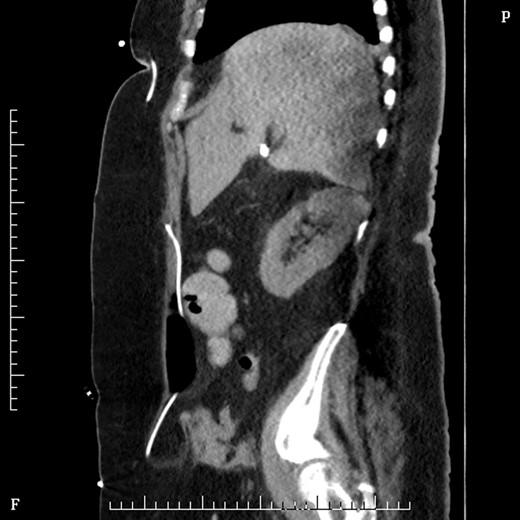

On Day 2 post VP shunt insertion, she was noted to be slow to recover and CT abdomen was performed. This demonstrated that the distal catheter tip was not in the pleural space but entered the abdomen and was redirected out along a tract into an umbilical hernia (Fig. 5). The following day she was taken back to theatre and the VP shunt was revised, and good visualization into the abdomen gave the impression that it was correctly in place. Repeat CT abdomen was performed to confirm placement and to our surprise the catheter had re-entered the same tract and travelled into the umbilical hernia (Fig. 6).

Coronal section CT abdomen after second shunt revision showing catheter again protruding out through umbilicus into hernia sac.